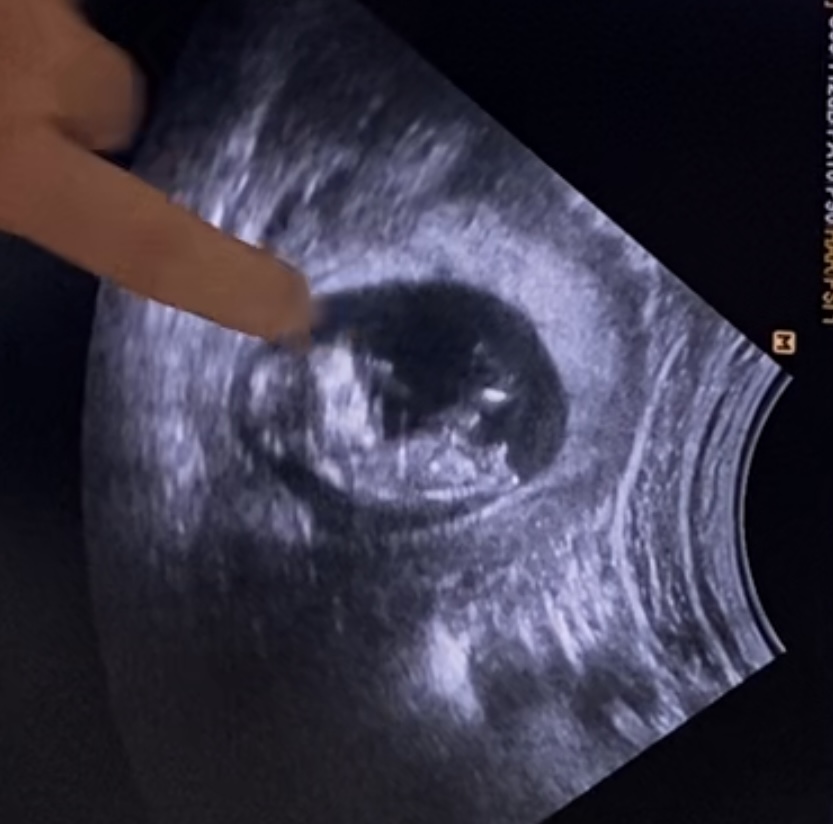

Podla vybezku je to chlapec, aj moj to takto presne mal a teraz v 20tt mi to dr potvrdil...

@whatever1 nie nie to pani doktorka niečo vysvetľovala( je to hlava) ten výbežok pipika na druhej strane v právo dole

Takze, neviem na koho názor das ale aj ja ktorá nikdy na ultrazvukoch na MK nič nevidí lebo sa v tom nevyznám ta aj ja tam vidím že chlapec 😂